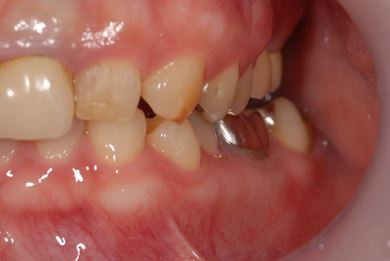

インプラントの症例写真 IMPLANT

| 性別/年齢 | 女性 / 30歳 | ||||||||||||||||||||||||||||||||

| 主訴 | 上の奥歯を抜歯すべきかどうか、抜歯する場合はインプラント治療が可能かどうかの相談。 | ||||||||||||||||||||||||||||||||

| 治療方針 | ソケットリフトにて上顎洞を拳上し、インプラント治療を可能にする。 | ||||||||||||||||||||||||||||||||

| 治療内容 | インプラント2本(ソケットリフト)、メタルボンドセラミッククラウン1本 | ||||||||||||||||||||||||||||||||

| 総治療費 | 1,011,675円 | ||||||||||||||||||||||||||||||||

| 治療期間 | 6ヶ月 |